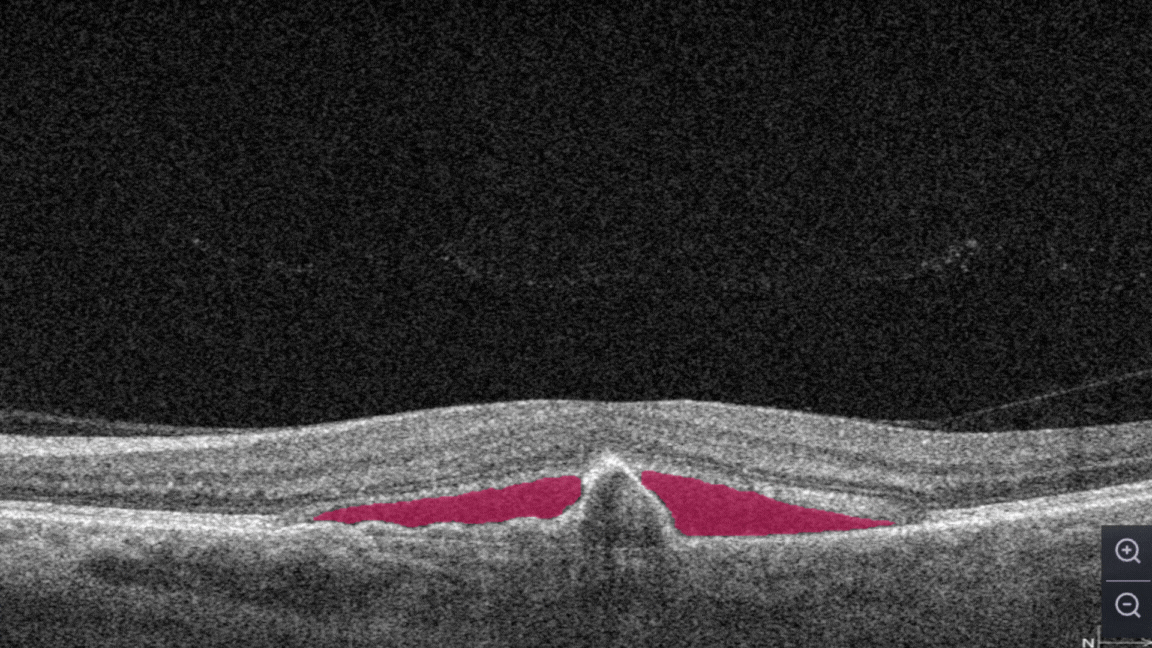

Subretinal fluid corresponds to the accumulation of a clear or lipid-rich exudate (serous fluid) in the subretinal space, i.e., between the neurosensory retina (NSR) and the underlying retinal pigment epithelium (RPE), in the absence of retinal breaks, tears, or traction

Fibrovascular RPE detachment. Delamination of the pigment epithelium of the retina is caused by the presence of newly formed vessels (fibrovascular membrane) under the RPE.